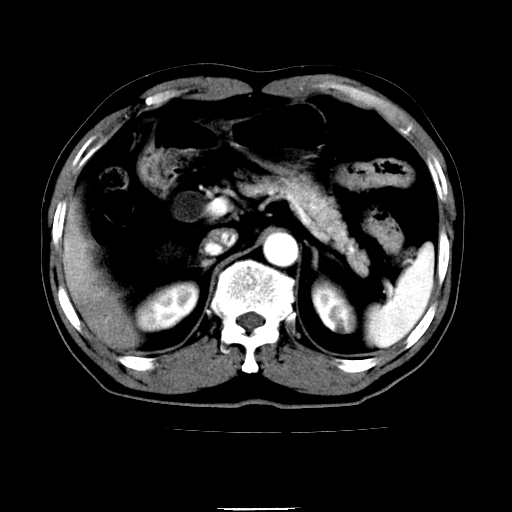

以下是引用chenqiong在2010-3-25 20:56:00的发言:[br]1、胆囊炎,胆囊息肉[br]2、肝内胆管及胆总管扩张,胆总管下端结石[br]3、十二指肠乳头旁憩室

以下是引用zxl51642在2010-3-26 10:47:00的发言:[br]胆囊炎,胆囊息肉,胆总管扩张,但未看到明显肿块,肝内胆管扩张不像恶性,炎性狭窄或阴性结石可能吧,建议mrcp,右肾小囊肿